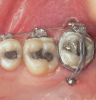

Fig 18. Bite interdigitation to finalize surgical orthodontic correction. After orthodontics, periodontal plastic surgery, bleaching, microabrasion, and restorative dentistry were performed.

Figure 18